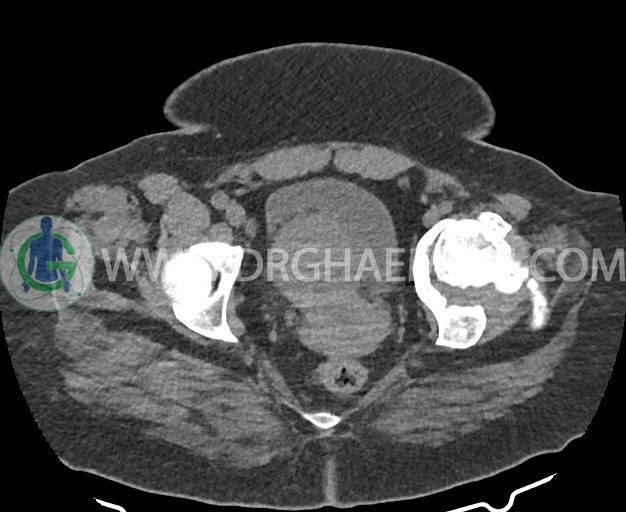

در سی تی اسکن اسپیرال شکم و لگن بدون کنتراست (مولتی دیدکتور 16 با مقاطع ظریف و بازسازی های ساژیتال و کرونال) :

ضایعه ای در مثانه و حفره لگن مشهود نیست.

شواهد استئوآرتریت ثانویه به صورت remodeling اسکلروز و کیست های ساب کندرال و کاهش فاصله مفصلی در کمپارتمان لترال hip چپ همراه با دفورمیتی استابولوم و خصوصا سر فمور و flattening آن دیده می شود.